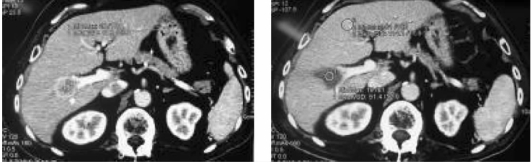

小肝癌的射频消融治疗前后图像对比,显示肝癌完全坏死